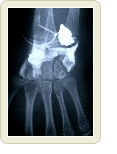

대퇴골 뼈 외측은 껍질부분에 해당하기 때문에 피질골(皮質骨)이라고 부른고, 내측 골수측에 있는 뼈가 해면골(海綿骨)이라 칭한다. 뼈는 단조로운 시멘트 덩어리 같은 물질이 아니다.

약 1cm두께의 피질골 속에 직경 200미크론의 원주가 가득 모여서 만들어진 모습을 상상하기 바란다. 현미경으로 단면을 보면 둥근 집합체로 보인다. 집합체의 뼈가 파괴와 생성을 반복하면서 유지되는 비밀이 있다. 200미크론의 작은 단위가 파괴와 생성을 반복하면서 뼈 건강을 유지한다.

내측 뼈인 해면골은 기둥의 대들보가 종횡으로 서 있는 구조를 이룬다. 이것이 뼈를 파괴시키며 뼈를 생성하는 세포이다.

그러나 50세부터 뼈가 감소한다 해도 60세까지는 큰 문제가 일어나지 않는다. 골절의 경우는 60세 이후에 나타난다. 척추압박골절은 65세부터 그리고 대퇴골경부골절은 70세부터 급격히 증가한다. 골량이 감소하는 시기에도 50 ~60세 사이에 대책을 세운다면 사전 예방이 가능하다.